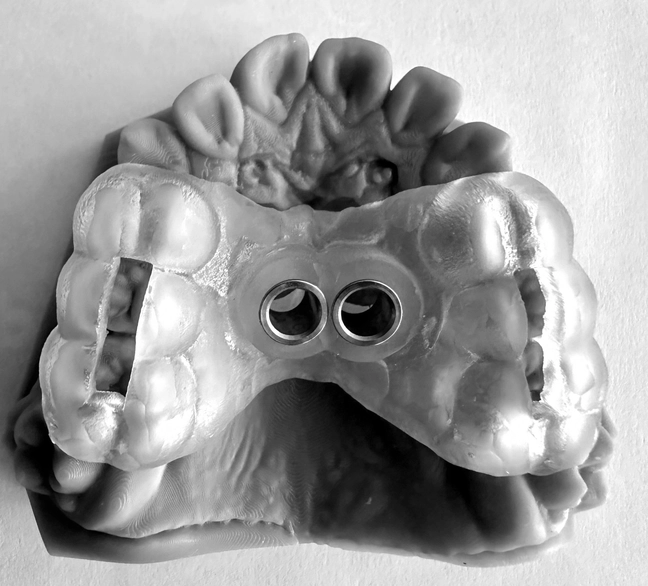

Anclaje esquelético MARPE guiado.

MARPE en adultos / Miniplacas Clase III.

3. XCROSS/EXPANSIÓN: La tercera llave es la integración. Cuando biomecánica, cirugía y tecnología se alinean, los límites desaparecen, se amplian las fronteras. Ni la edad ni la complejidad son barreras cuando hay protocolo guiado. Lo que antes era imposible, hoy se resuelve con confianza.